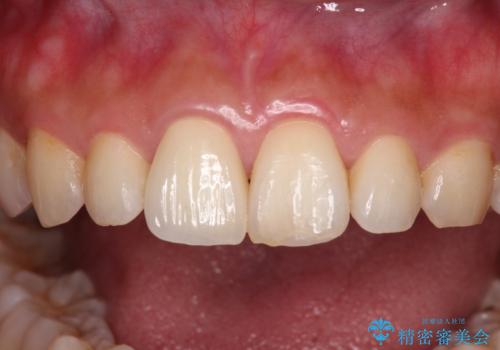

転んで欠けてしまった前歯 オーダーメイドのオールセラミッククラウン

オーダーメイドタイプのセラミッククラウンは、既製タイプのク色のラウン(スタンダードタイプ)とは異なり、色合いが合うまで何度も修正を行って調整をいたします。